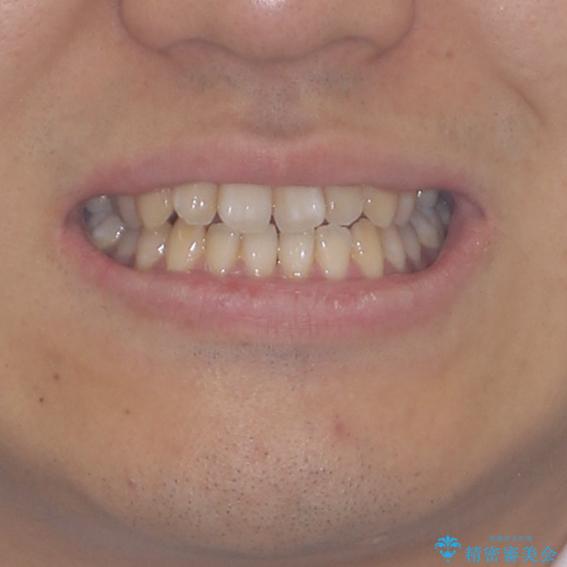

下顎前歯と上顎の部分矯正

- 上下の前歯の叢生を気にして来院された患者様です。

前歯のみの矯正治療を希望でしたが、上顎臼歯が舌側転位していたため、上顎は全体を、下顎は前歯のみを矯正治療することとしました。